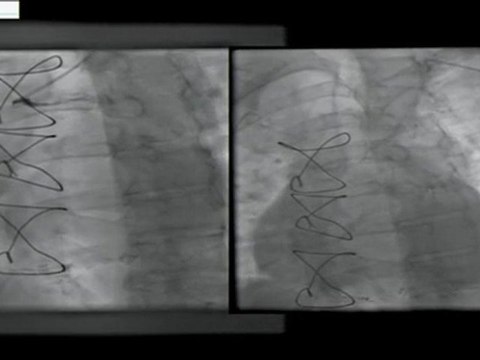

tibio, peroneal, artery, atherectomy, rotablator, antegrade, approach, incathlab